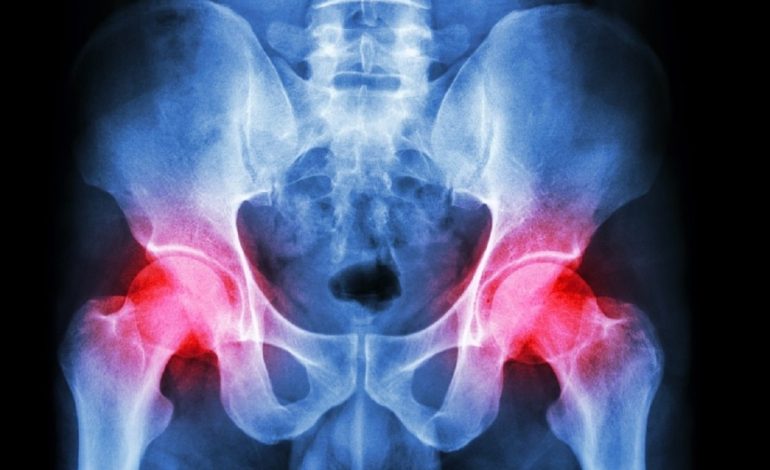

Una prótesis de cadera reemplaza la articulación deteriorada cuando los tratamientos convencionales no alivian el dolor. Este procedimiento es exitoso en muchos casos, permitiendo que las personas retomen una vida activa. El implante está compuesto por varios componentes como una bola, un vástago y un acetábulo que restauran el movimiento.

Sin embargo, aunque la recuperación es generalmente positiva, la prótesis no tiene la misma flexibilidad ni resistencia que una cadera natural. Esto puede limitar la capacidad de realizar ciertos trabajos que requieran movimientos bruscos, cargar peso excesivo o mantener posturas incómodas durante largos períodos.